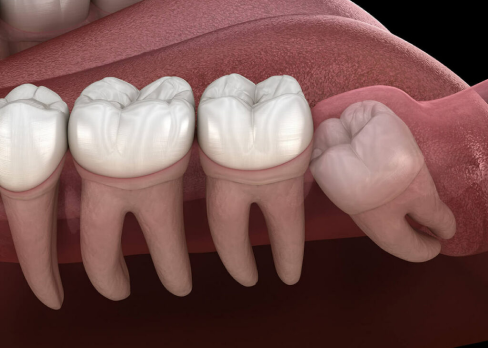

Wisdom teeth removal is a surgical dental procedure in which one or more wisdom teeth are extracted. These teeth may be impacted (trapped under the gums or bone), partially erupted, or misaligned. Removing problematic wisdom teeth helps maintain oral health and prevents future dental complications.

The first step is a detailed clinical examination and digital X-ray to assess the position of the wisdom tooth and surrounding structures. The second step involves administering local anesthesia to ensure a painless procedure. In some cases, sedation may be recommended. The third step is the surgical removal of the wisdom tooth. If the tooth is impacted, a small incision may be made in the gum and bone to safely extract the tooth. The final step includes cleaning the area and placing sutures if required. Post-operative instructions are provided to support proper healing.